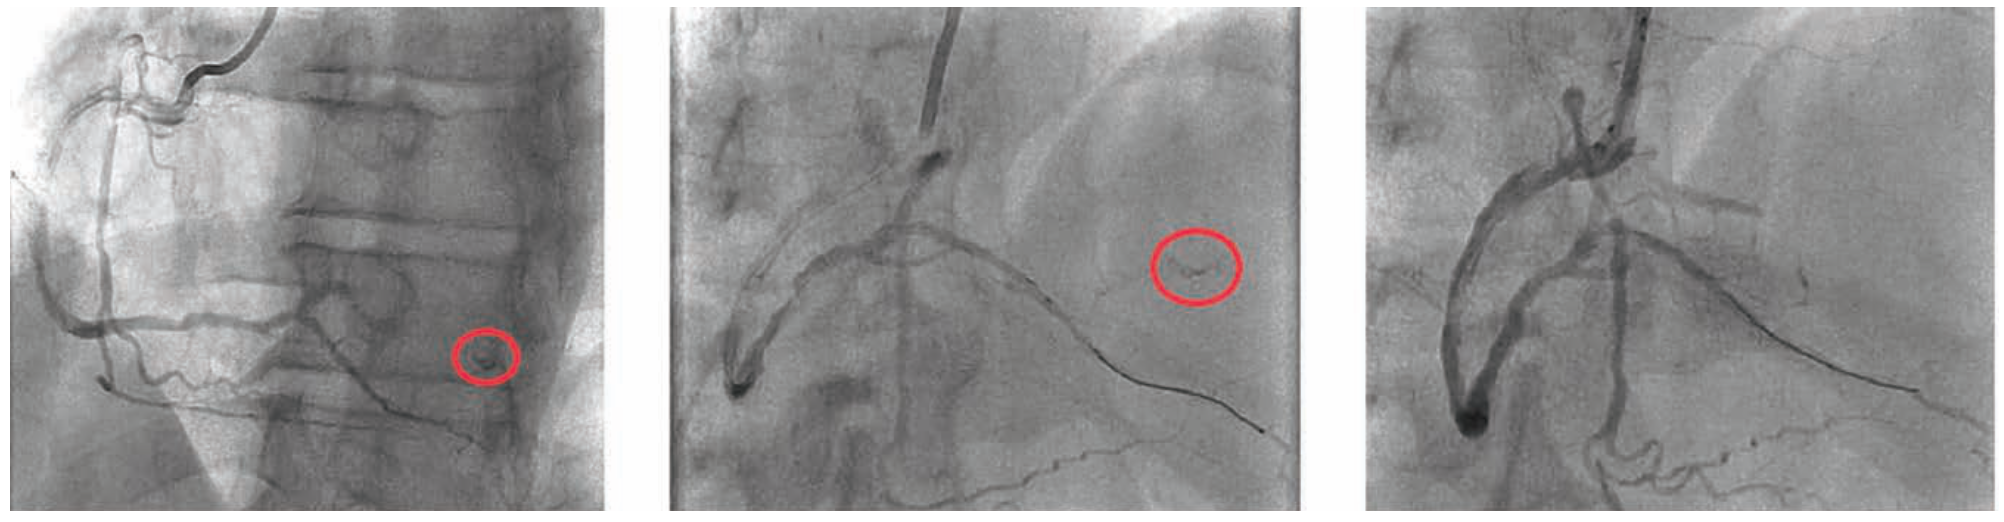

We then attempted to re-place the aforementioned 3.0 mm x 38 mm Synergy XD drug-eluting stent into the vessel; however, as the deployment attempt began, we could see that the balloon was not filling and the stent would not deploy. We attempted to remove the device from the coronary artery and out of the guiding catheter, but the stent shaft was entirely disrupted. In attempting to remove it, the distal stent and balloon and distal aspect of the shaft remained in the coronary in the ascending aorta, while the proximal aspect of the shaft was entirely free and so unexpectedly came out altogether (Figure 5). We attempted to snare the undeployed stent that was still on the wire with a Goose Neck snare (Medtronic), but were not able to get it past the undeployed stent, which was well seated on the stent deployment balloon. We placed a new .014-inch BMW wire distally past the stent, hoping to wrap it around the wire that was in the vessel distal to the stent and create a distal braid with both wires to pull the system out. However, we were not successful in gaining an adequate distal purchase. A Trapper balloon (Boston Scientific) was inflated in the distal aspect of the guide, trapping the distal stent shaft. Now trapped as a unit with the guide catheter, the distal stent shaft with the undeployed stent on the wire was removed without difficulty from the 6 Fr Slender sheath (Terumo) (Figure 6).

Stent shaft fracture and disruption is a rare occurrence during stent deployment. Various strategies have been utilized to remove the retained segment, including grasping the distal-most segment with a Goose Neck snare,1 attempting to place a wire or wires distally to make a braid to pull back the segment into the guiding catheter, or trapping the distal shaft within the guide with a trapping balloon.2,3 In our case, the last strategy proved effective and allowed for safe resolution of the procedure.